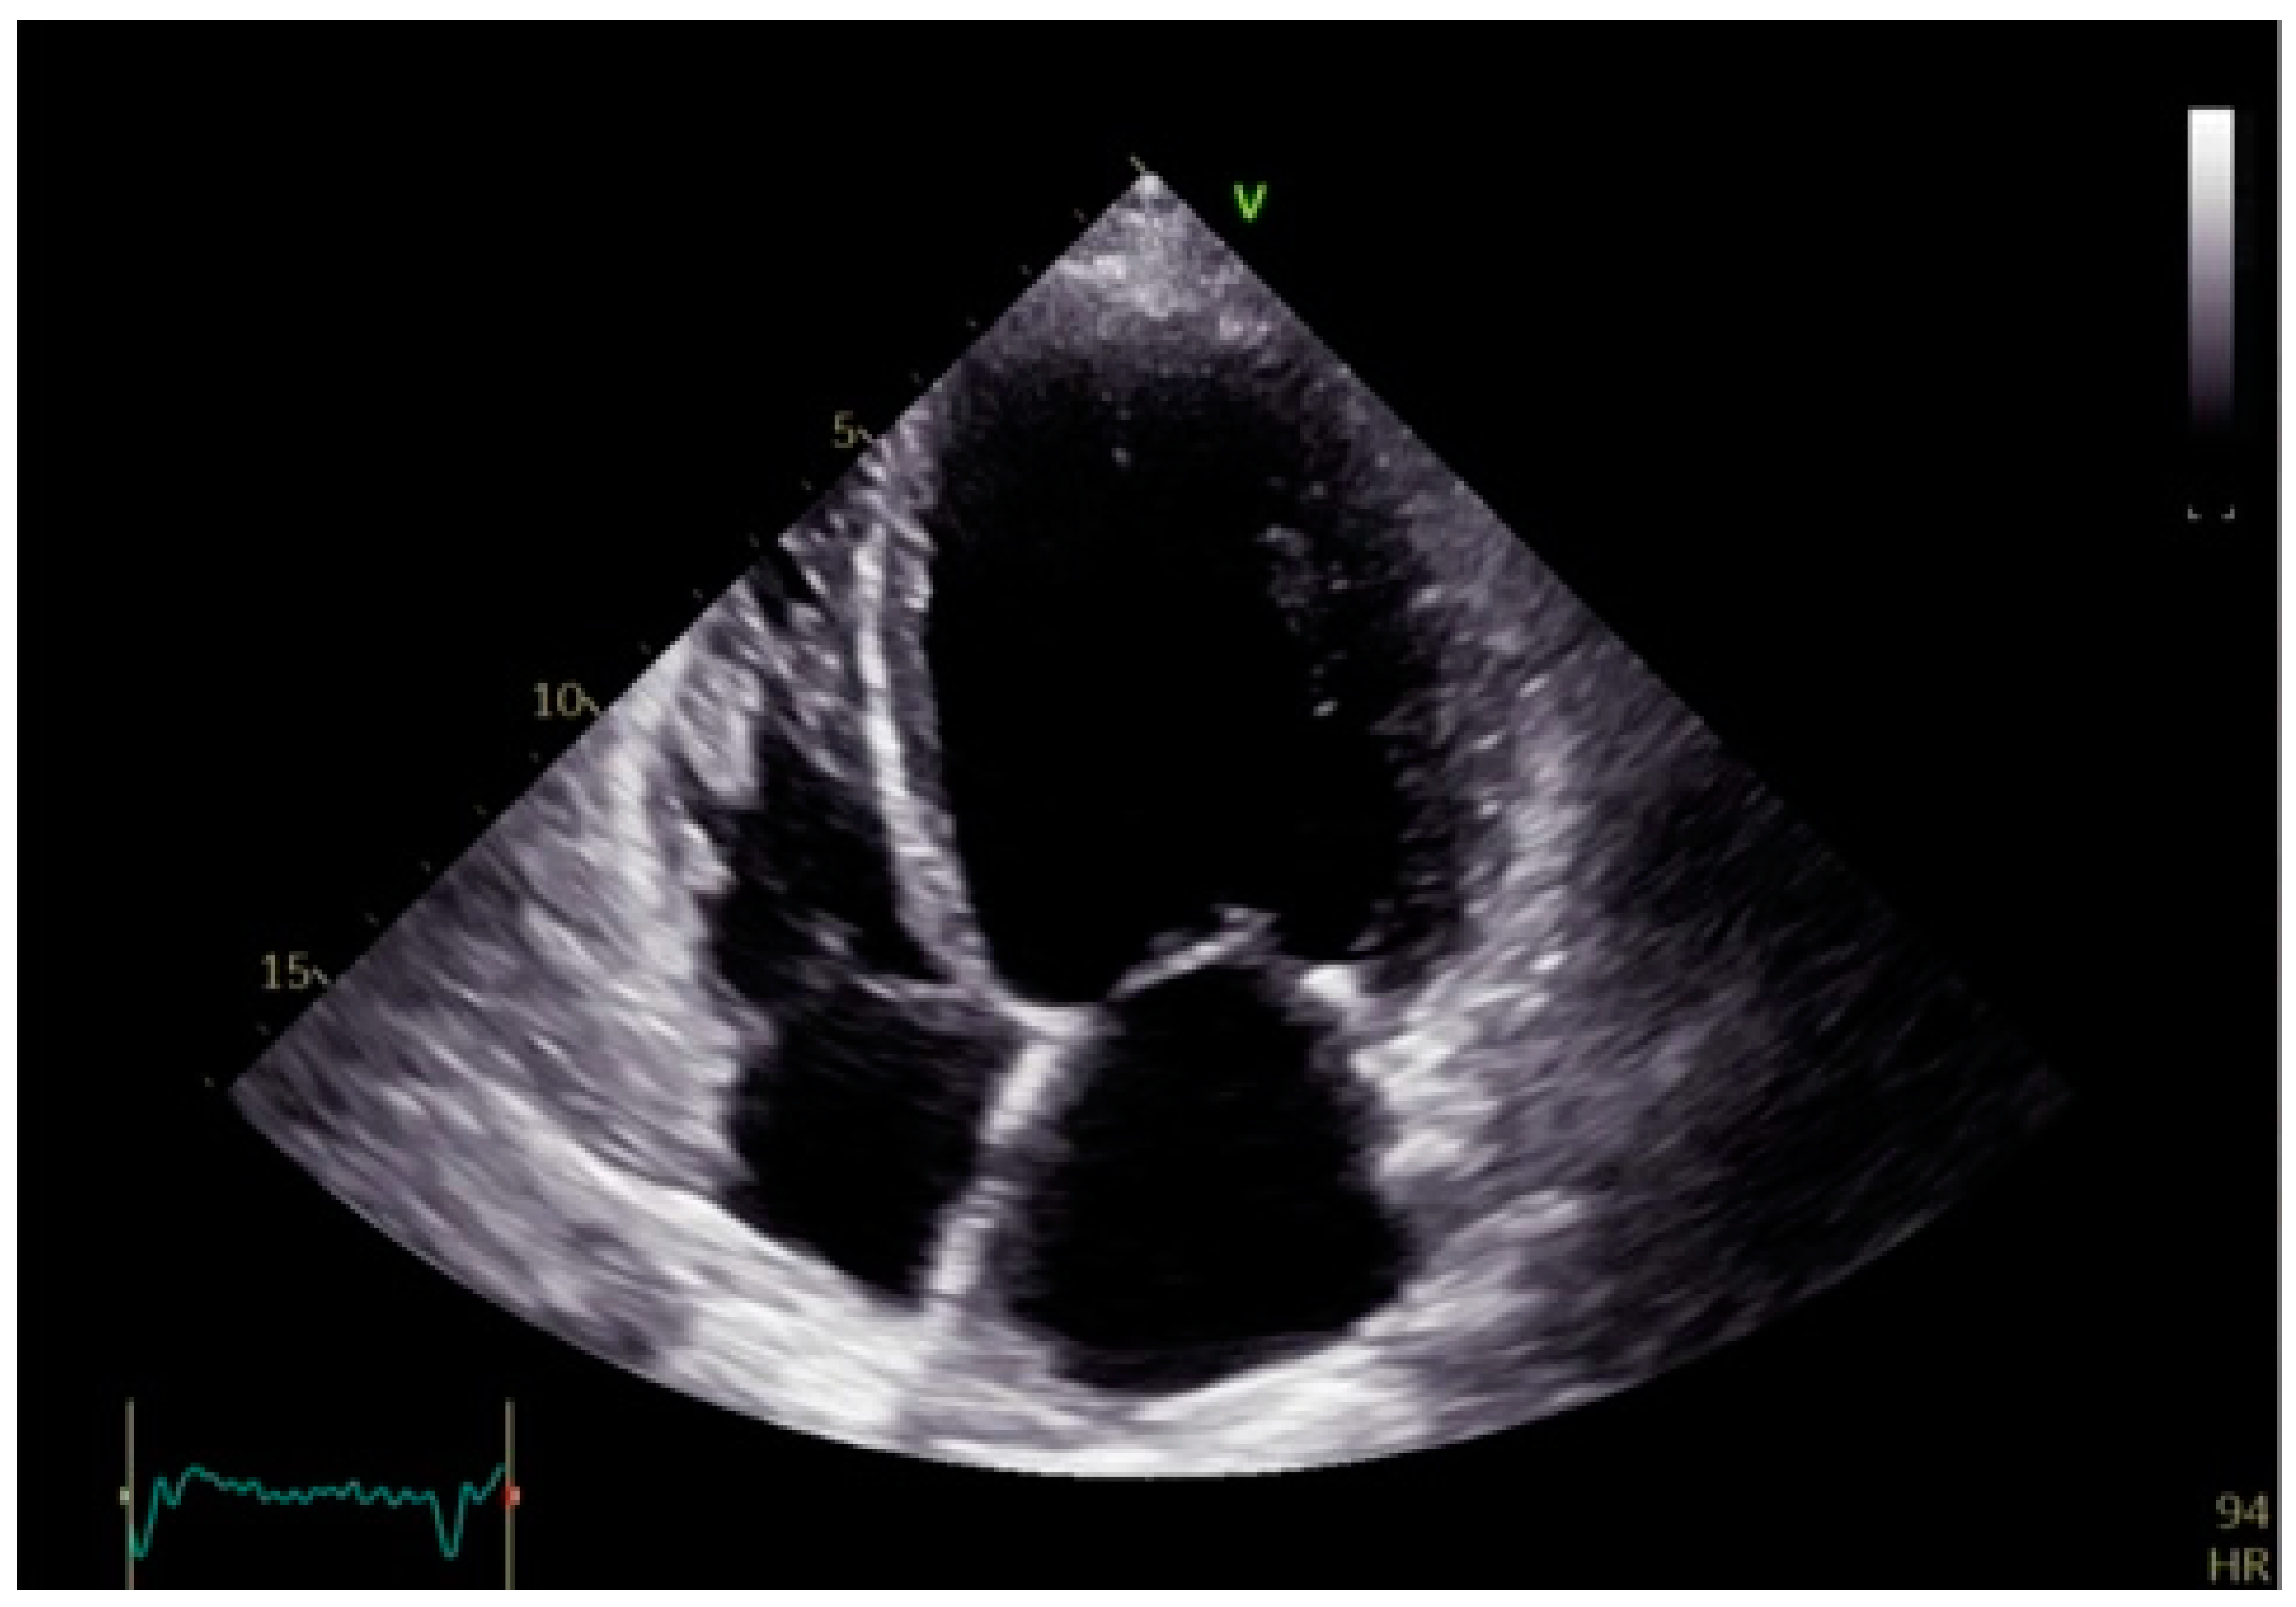

- Mei, Y.; Han, R.; Cheng, L.; Li, R.; He, Y.; Xie, J.; Wang, Z.; Wu, Y. Assessment of Cardiac Function and Ventricular Mechanical Synchronization in Left Bundle Branch Area Pacing by Speckle Tracking and Three-Dimensional Echocardiography. Am. J. Cardiol. 2023, 187, 1–9. [Google Scholar] [CrossRef]